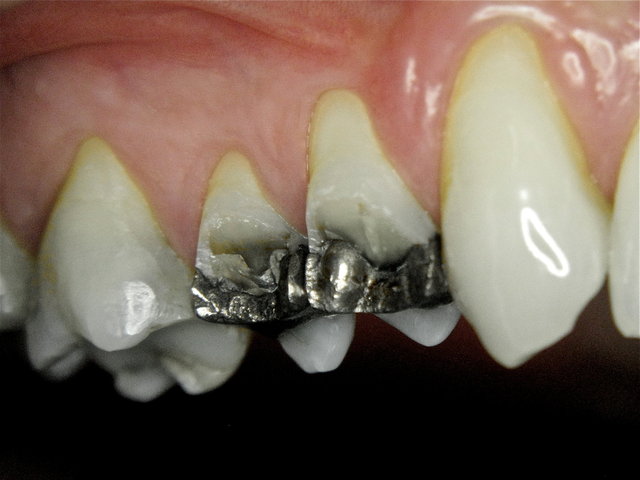

Alte Amalgam-Füllungen mit Sekundärkaries ...

Composit-Füllungen by CLINICDENT ✓